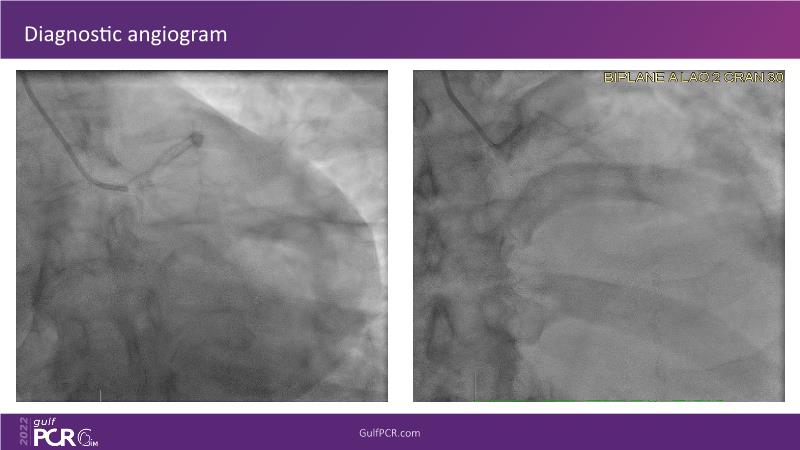

OCT and artificial intelligence: a new shiny light for better decision making in complex coronary interventions

Watch this case-in-point presentation focusing on decision-making in complex PCI using OCT plus AI to understand how to take the right measurement throughout the procedure, how artificial intelligence aids in decision making during imaging-guided PCI, and to gain skills in interpreting OCT imaging, among others!